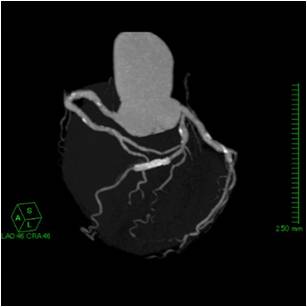

心筋梗塞や狭心症を引き起こす原因は、心臓周りを取り巻く血管(冠動脈といいます)の内部が狭くなったり閉塞したりして血液供給が不十分になり発生します。

冠動脈の診断で最も信頼できる検査として心臓カテーテル検査があります。しかし、カテーテルを血管内に挿入する検査であり、合併症や検査費用、入院の必要性があったりと心配な材料もあります。

X線CTでの心臓検査は、造影剤を腕から入れて、数秒間の撮影を行うだけで検査が終わりますので日帰り検査も可能であり、被ばくの心配等も少ないです。